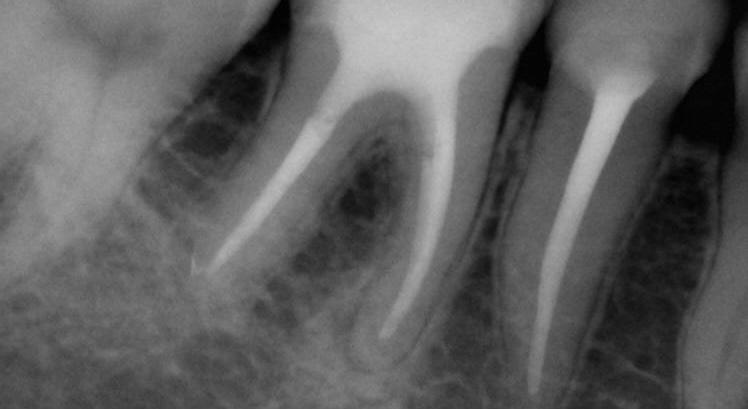

Endodontically treated molars with conservative access do not require a post. Of course, the final treatment does not only depend on the access type, but also on the size and depth of the cavity. Here, FRC have also proven their worth in complicated cases with internal resorptions (Figs. 5-8).

5: Pre-operative situation with large defect and internal resorption (a) Intraoral view (b) X-ray

Fig. 7: Final X-ray.

Fig. 9: Pre-operative X-ray.